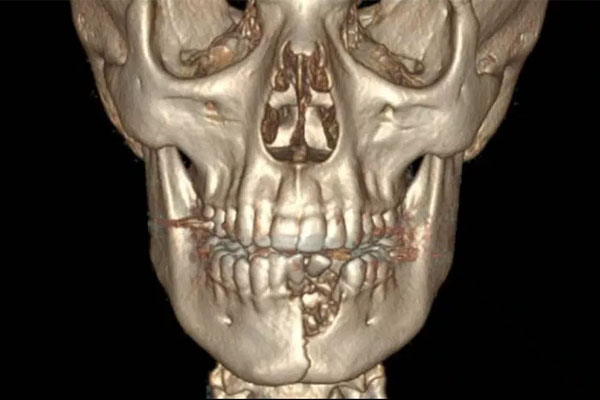

Al joven Austin, entonces de 17 años, le explotó su dispositivo mientras fumaba, provocándole una severa lesión en la mandíbula.

Austin tenía un agujero en la barbilla y perdió varios dientes.

Katie W. Russell, la cirujana pediátrica que atendió a Austin, comparó sus lesiones con las de “accidentes automovilísticos de alta velocidad”.

Por otra parte, su colega Jonathan Skirko comentó que parecía “una especie de herida de bala a corta distancia”.

Las lesiones de Austin requirieron dos cirugías, que incluyeron agregar una placa de titanio para estabilizar su quijada y coser las heridas.